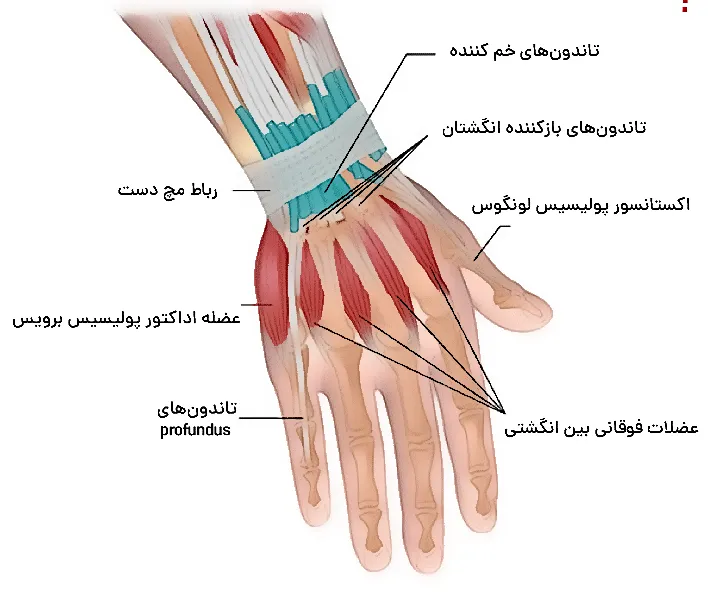

آناتومی تاندون دست

تاندون دست به دو نوع مختلف تاندونهای فلکسور و اکستنسور دستهبندی میشوند. تاندونهای فلکسور موجب خم شدن انگشتان و تاندونهای اکستنسور نقش مهمی در باز کردن انگشتان دارند.

آناتومی تاندون های دست